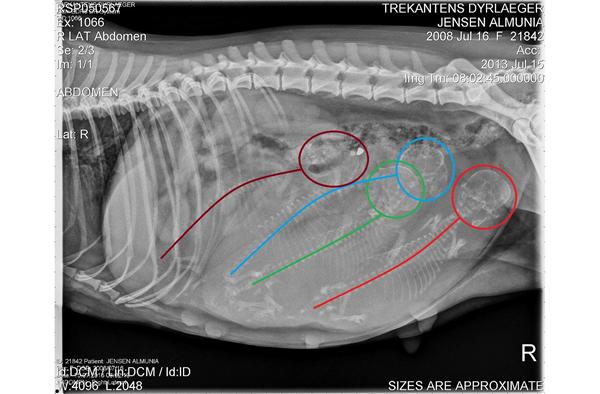

I mandags blev Almunia røntgenfotograferet, hun var på dag 58 fra første parring.

Jeg kan godt forstå at mange synes de kan se 5 hvalpe, men det snyder; der er altså "kun" 4 vapsere.

Jeg ser det så som at grøn og blå skal bytte kranier ud fra din tegning.

Forestil dig at blå rygrad ligesom krummer og ligger med øjnene nedad imod midten af maven, hvis det giver mening?

Og det er der jeg ser de fire.

Så ser også kun fire rygrader og fire kranier.